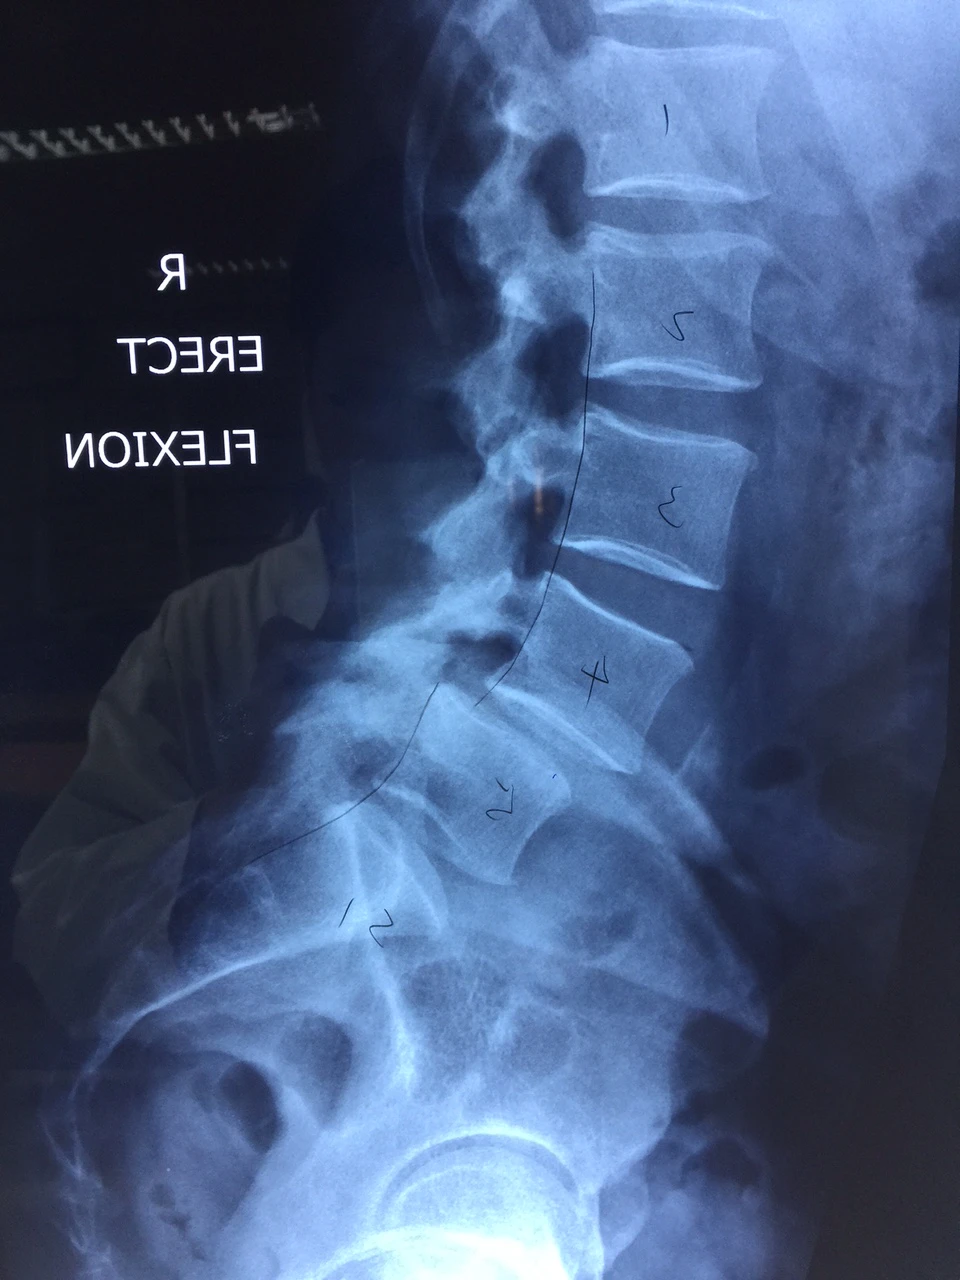

Bệnh nhân bị đau buốt vùng thắt lưng nhiều năm. Đau tăng khi vận động như đi lại, mang xách vật nặng. Các cơn đau ngày một tăng dần gây ảnh hưởng nhiều đến hoạt động sinh hoạt hằng ngày. Do vậy, bệnh nhân đã đến BV Việt Đức khám, chụp X-quang.

Qua hình ảnh chụp chiếu, BS được biết bệnh nhân bị trượt đốt sống nặng, cột sống thoái hóa nghiêm trọng, xẹp toàn bộ chiều cao đĩa đệm…